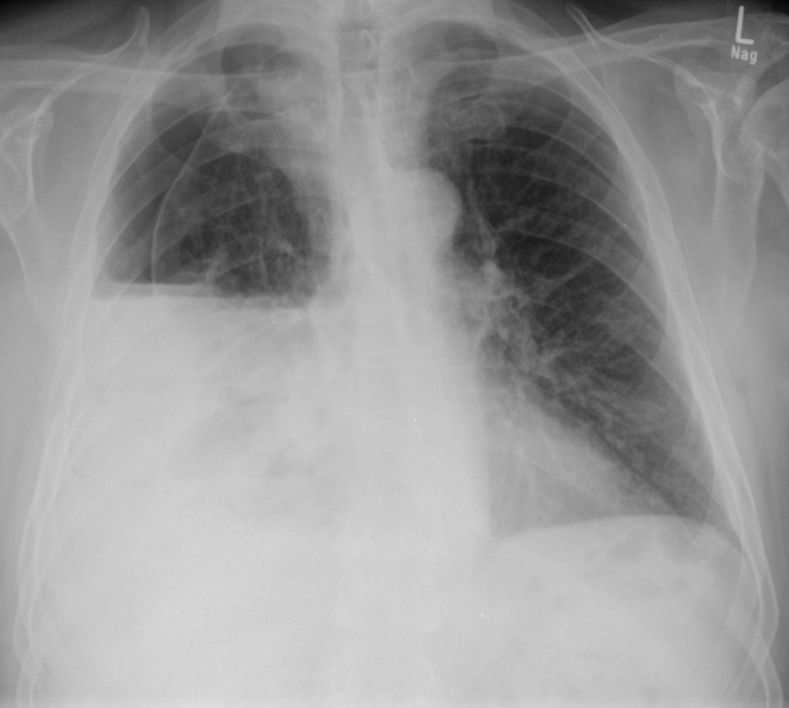

Röntgen Thorax Primärtumor im rechten unteren Unterlappen T2N3Mo. Nur diskrete Verdichtung im rechten unteren Hilus.